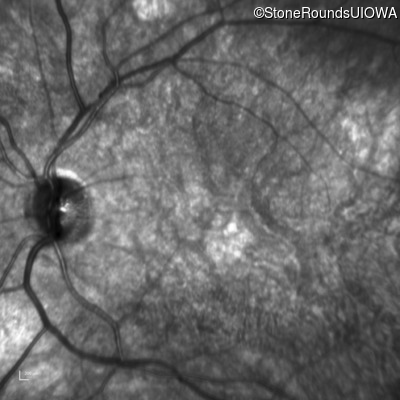

Infrared Fundus Photograph - Right - 20/100

Exemplar